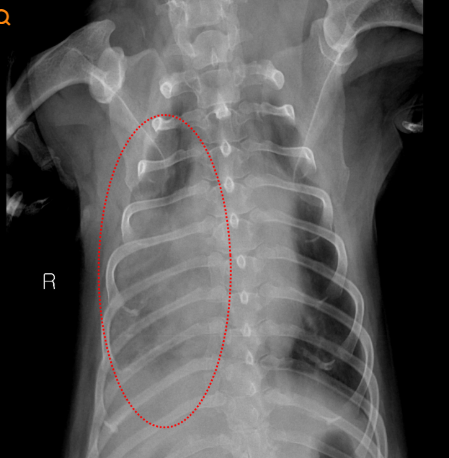

- 정기 흉부 X-ray + 심장 초음파